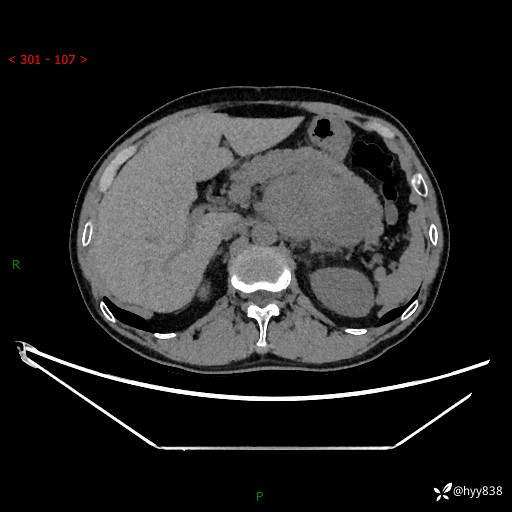

年龄:61岁

主诉:发现腹膜后肿瘤3天

腹部CT平扫+增强(动脉期+静脉期)